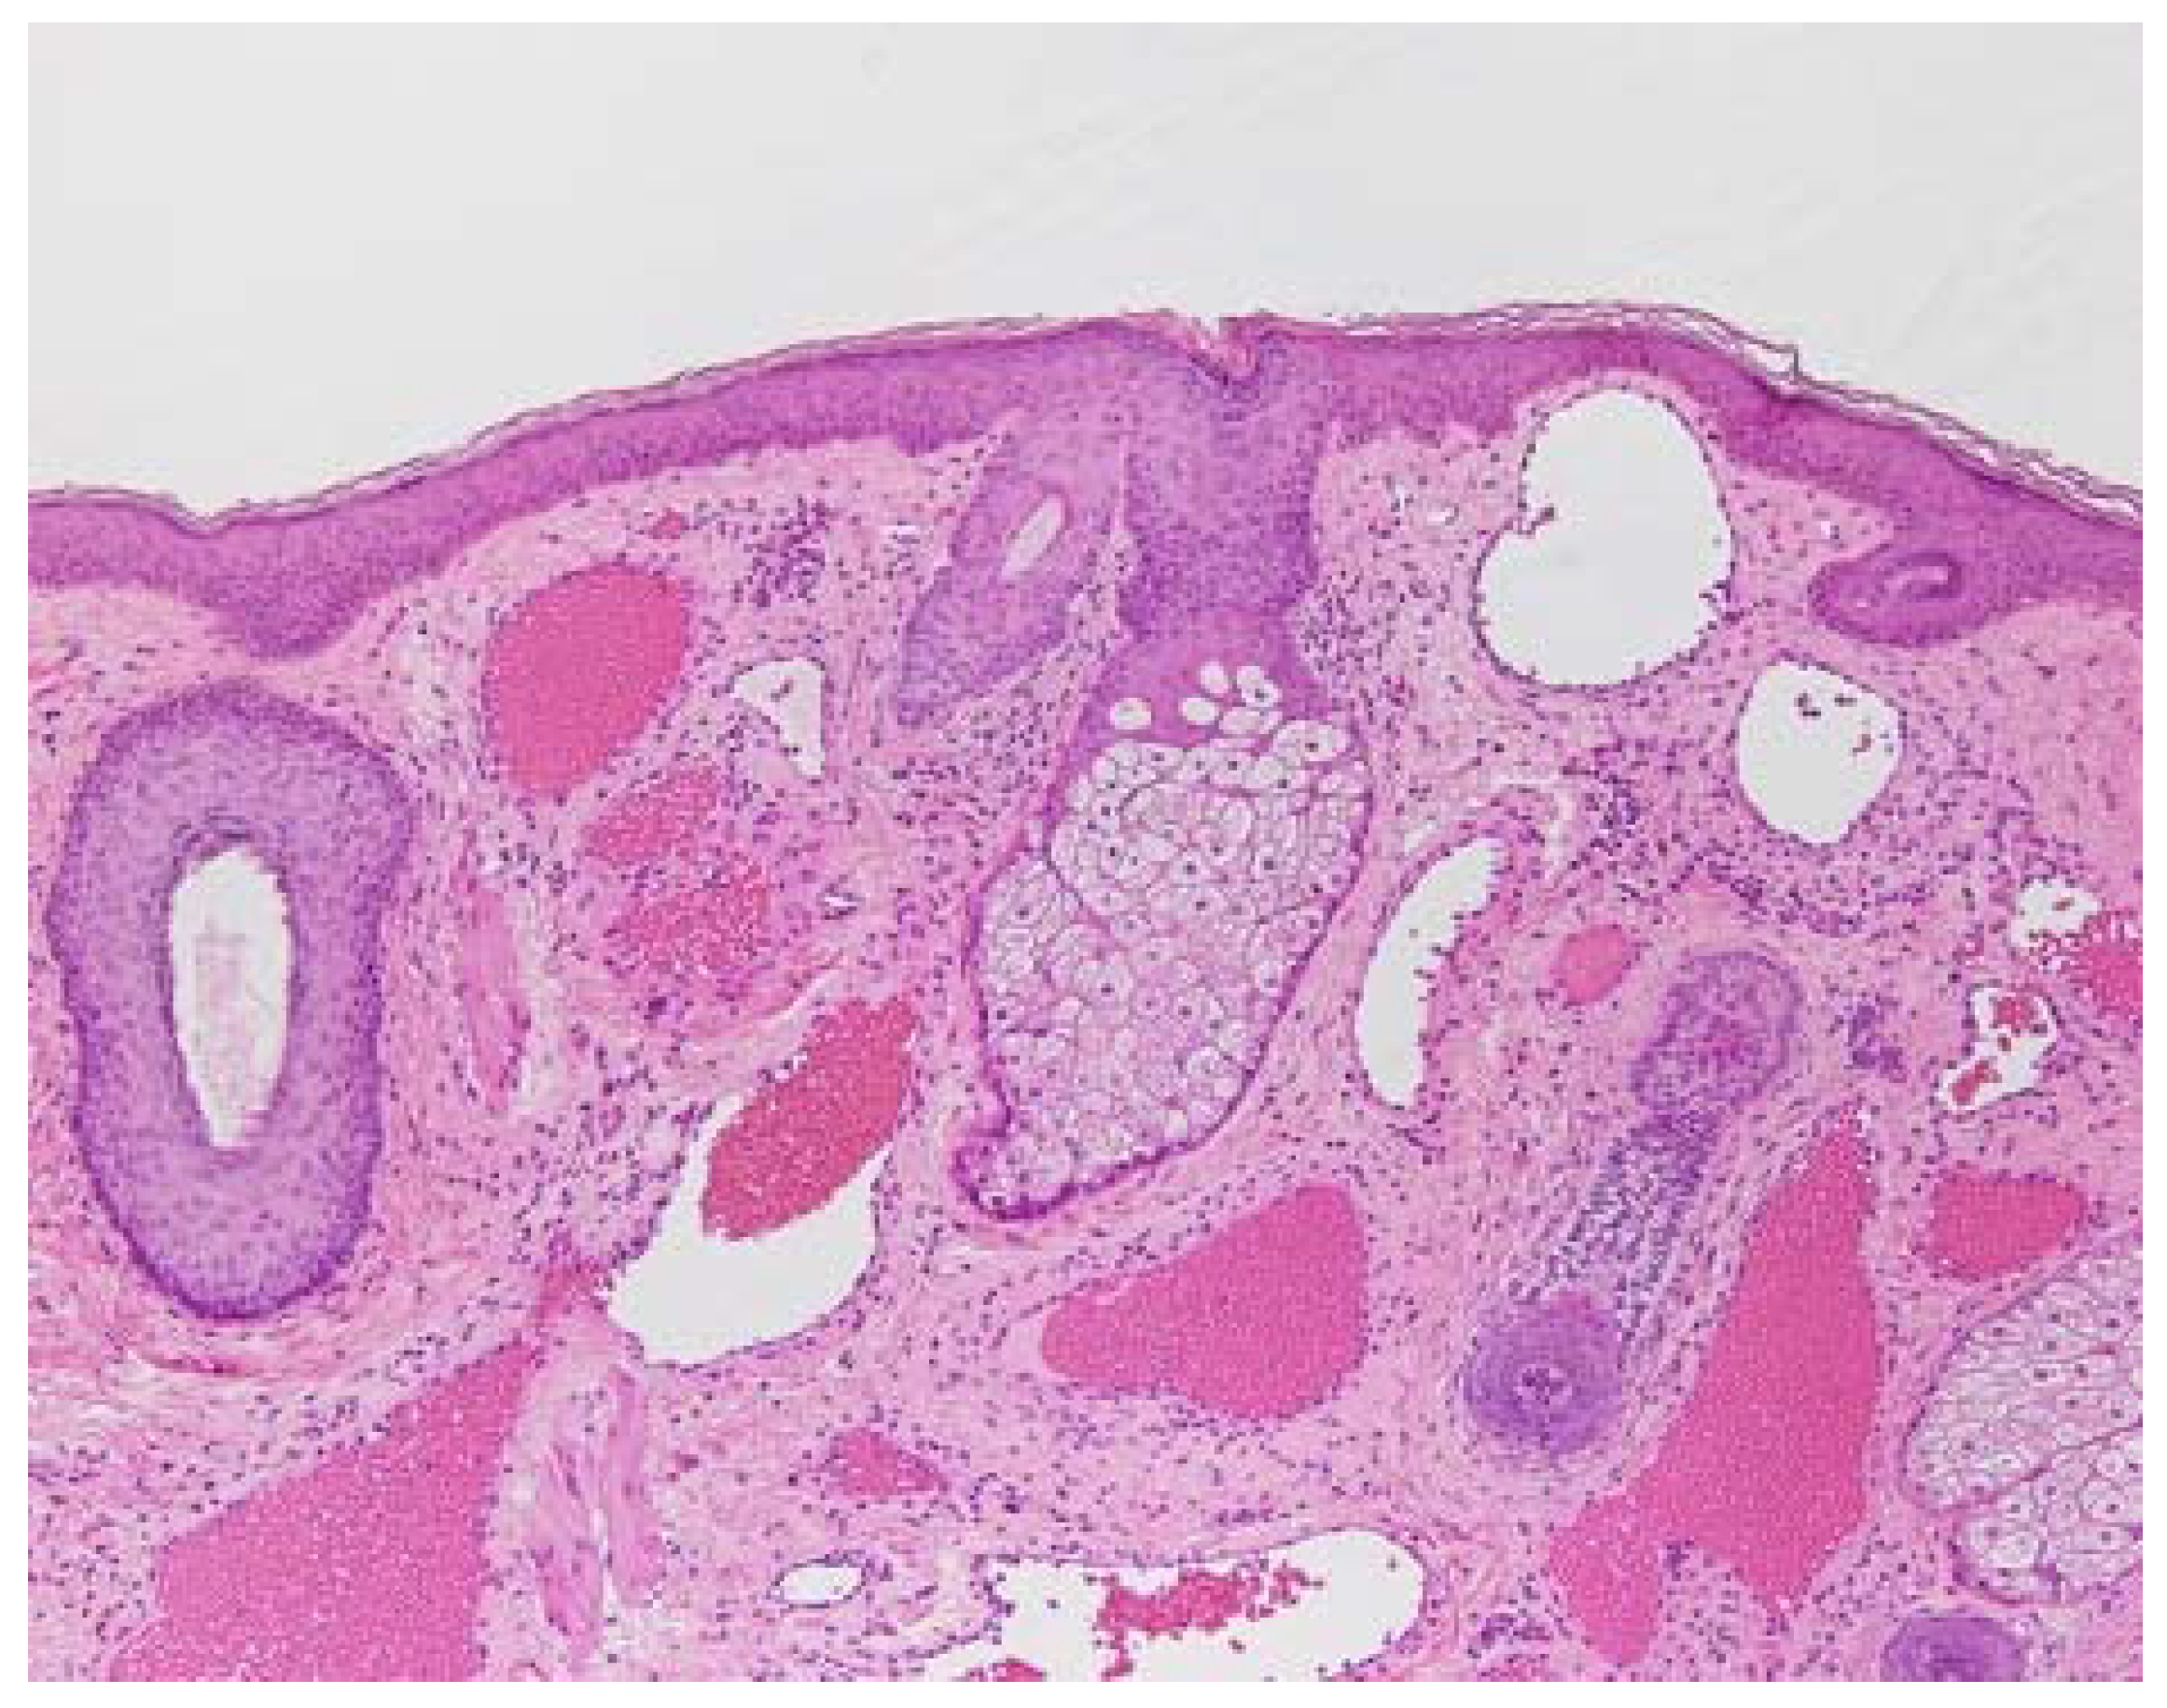

2. Pathology of Port-Wine Stains

5.3. Changes in Chicken Wattle Microvessels with Dye Laser Irradiation after Hb-V Intravenous Injections